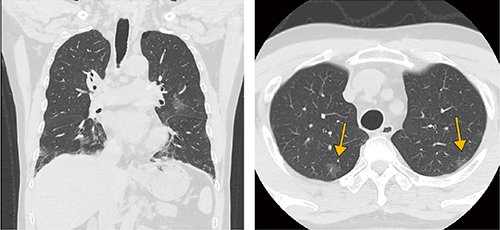

■Aquilion Lightning / Helios i EditionによるCOVID-19肺炎画像

AiCE-iを用いることで肺野内のノイズを大幅に低減。COVID-19初期の画像所見である淡い陰影(↓)が明瞭に確認できる。